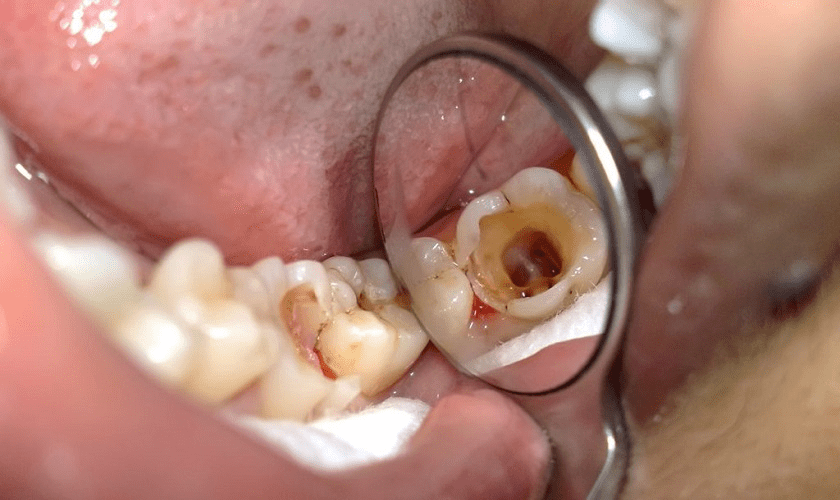

Turning 60 often means facing unexpected hurdles that no one warned you about. A 2023 survey reveals 60% of seniors report tooth sensitivity, while 50% battle cavities or gum issues. It’s frustrating when a cold drink makes you wince or you dread another dental bill—sound familiar? But it’s not just discomfort. Cavities can lead to tooth loss, persistent pain, and even lower confidence that ripples into how you smile at family gatherings or enjoy meals with friends.

Benefit 1: Prevents Cavities

Meet Susan, 66, a retired teacher from Ohio who spent years wincing through family dinners. Tooth pain made eating tough. “I felt anxious every time I bit into something,” she said. After swishing coconut oil daily for just two weeks, her cavities reduced noticeably. A 2021 Journal of Dental Research study suggests coconut oil’s lauric acid may reduce cavity-causing bacteria by 15%. It works by disrupting plaque at the source.